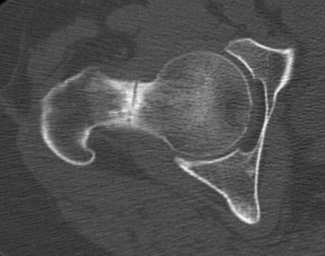

CT demonstrating incomplete fracture at inferior neck

CT demonstrate likely complete fracture, with some displacement